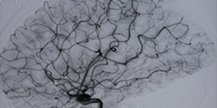

腦動靜脈畸形(arteriovenous malformation,AVM)是腦血管發(fā)育異常所致畸形中最常見的一種。占腦血管畸形90%以上。畸形血管是由動脈與靜脈構(gòu)成,有的包含動脈瘤與靜脈瘤,腦...>>詳細(xì)